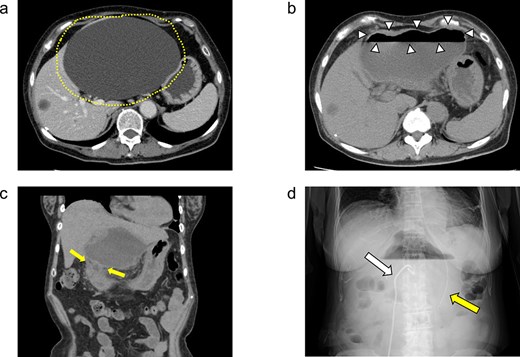

She was discharged home uneventfully on the 10th day after the surgery. CT has identified no evidence of recurrence 6 months postsurgery (Fig. 4).

Plain CT image 6 months after the patient’s surgery. There was no evidence of hepatic cyst recurrence.